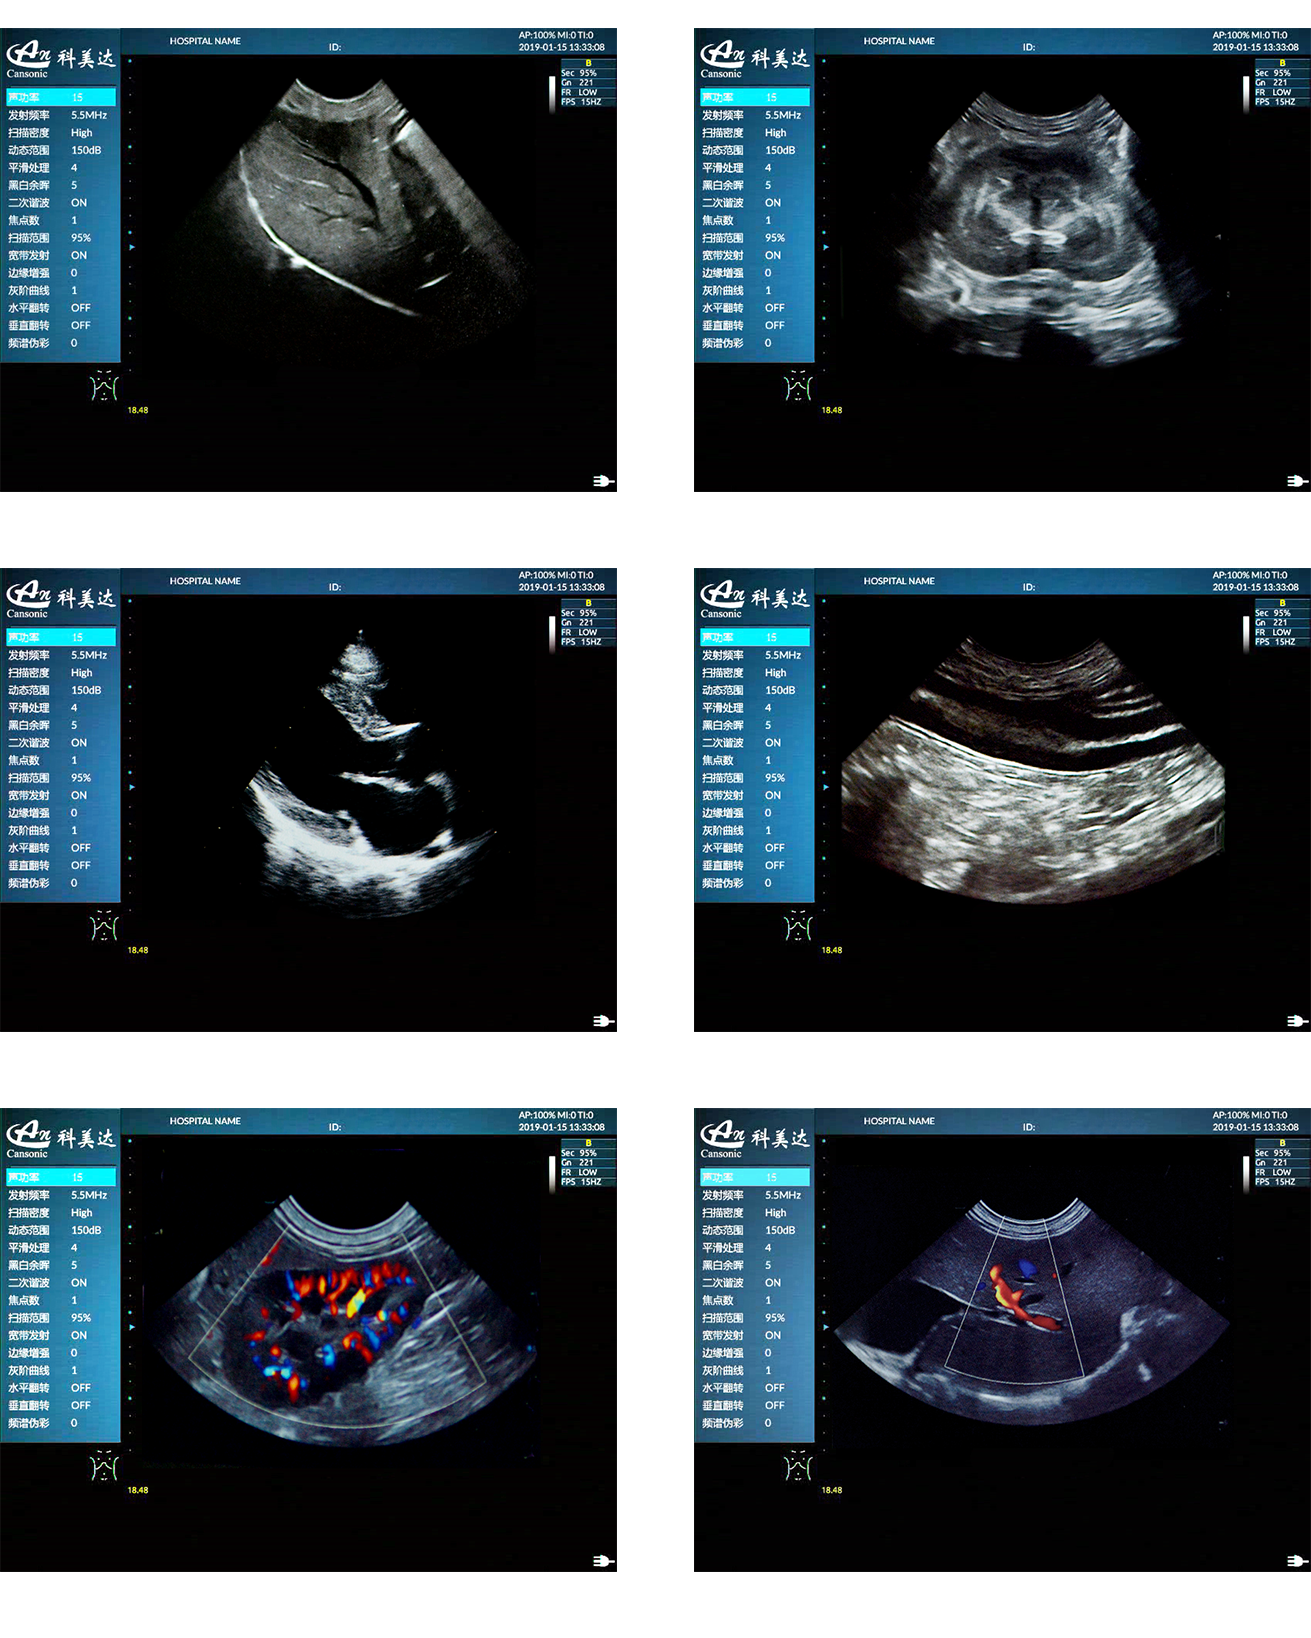

臨床圖示